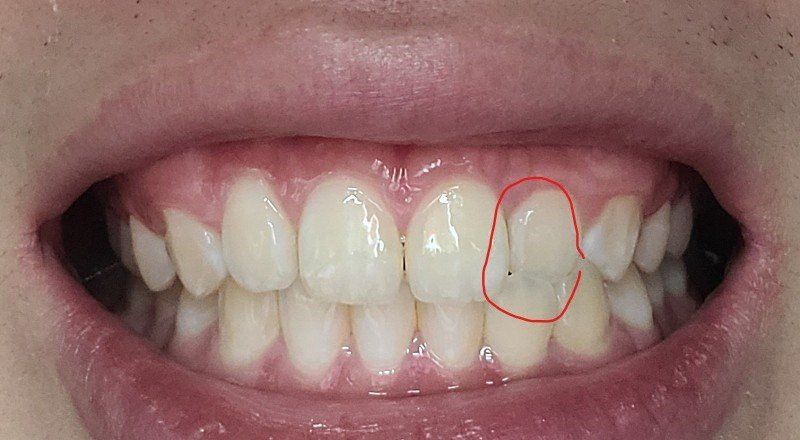

송곳니랑 그부근 어금니가 좀 더 틀어져서 깊게?물려요 턱이 비대칭이있긴한데 이정도비대칭은 사람마다 있다고들 하는데

-한쪽 송곳니은 살짝 떠있고 반대쪽은 잘물려요

왜 그런건지 모르겠어요 중심선이 안 맞아서 그런 건가요?

앞니 옆쪽 치아하나도 위아래가 부딪힙니다